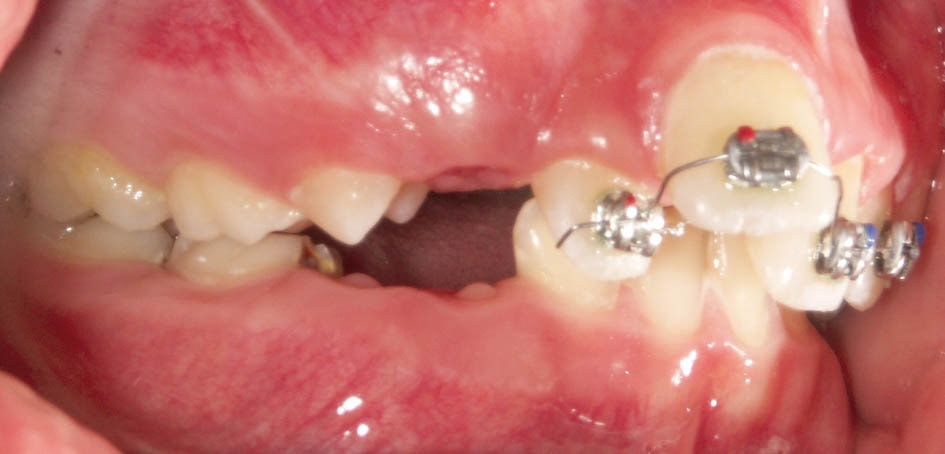

گاهی بیمار شما Div2 است و بخاطر رترودشدن انسیزورهای بالا و دیپبایت شدن بیمار دیگر اورجت ندارید. بیمار مندیبل را در زمان تهیه موم باید جلو بیاورد و چون اورجت ندارید این کار عملی نیست، لذا باید ابتدا اورجت بسازید و بعد موم بایت بگیرید (شکل 72-5 و 73-5).

شکل 72-5: بیمار کلاسII و دیپ بایت است.

در این مواقع باید دندانهای قدامی را پروترود کنید. میتوانید یک پلاک آکریلی بسازید و Z Spring پشت قدامیها میگذارید یا چند تا براکت با یک سیم 0.012 سوپرالاستیک بگذارید. طبیعی است که گذاشتن چند براکت (شکل 74-5 و 75-5) خیلی سریع و در کمتر از 2 ماه جواب میدهد و نیاز به همکاری از جانب بیمار خیلی کمتر است.

شکل 74-5: چسباندن چند براکت و قراردادن سیم 0.012 سوپر الاستیک برای ساختن اورجت (تبدیل بیمار کلاس II/2 به II/1).